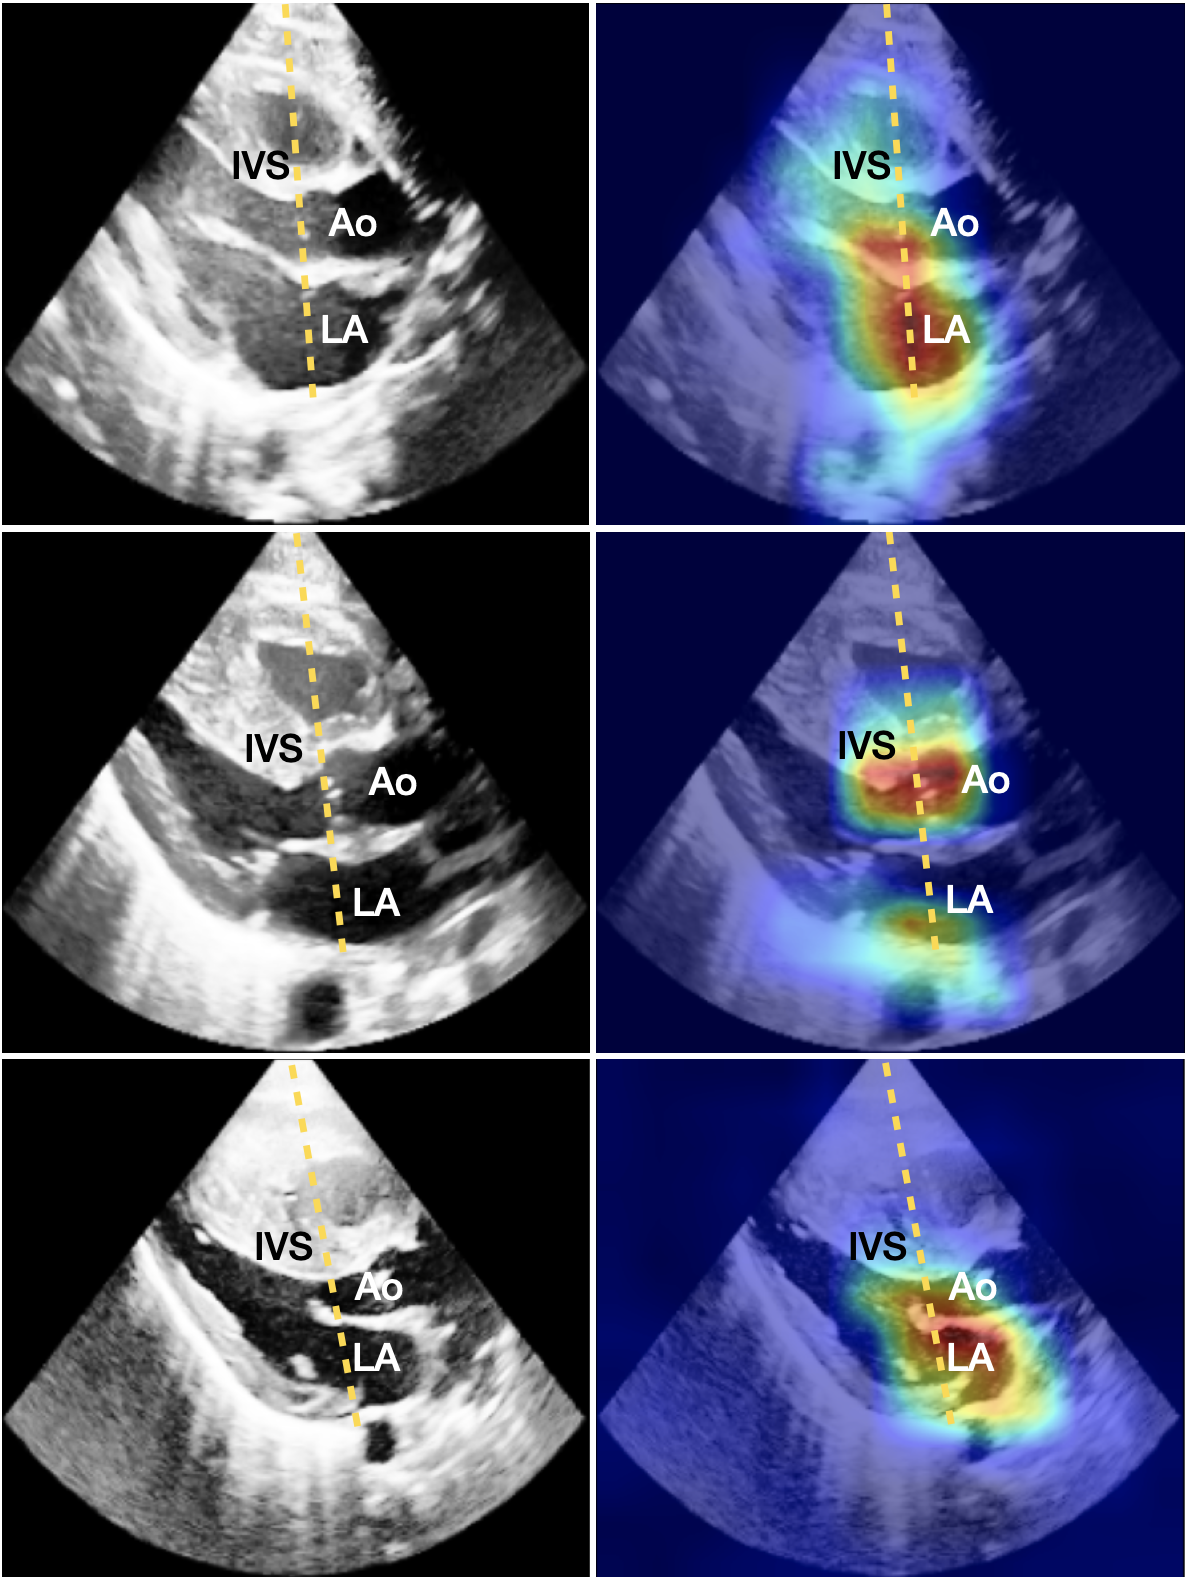

To increase the clinical usability, our method contains a post-hoc analysis of the single-view spatio-temporal convolutions. For each ECHO view, we highlight the pixels that are the most relevant for the assessment of PH severity. In Fig. 2 we show the original ECHO frames with different levels of PH (left column) combined with saliency maps using Grad-CAM (right column) corresponding to the significant views, in (a) PSAX-P and in (b) PLAX.

Subjective evaluation of the IVS morphology is also possible from the PLAX view [9]. Furthermore, quantitative assessments are frequently performed on this view, including measurements of the aortic valve (AV) annulus diameter, and left atrial-to-aortic root diameter ratio (LA:Ao) by extracting the M-mode as demonstrated with the yellow line in Fig. 2(b). When exploring the saliency map of the PLAX severity model, we see in Fig. 2(b) that the model focuses on the area around the LA, AV and Ao, and IVS. This suggests that the model is able to consider both the relevant quantitative features and the subjective ones.

(b) PLAX

Figure 2: ECHO frames of subjects with no, mild and severe PH (left), as well as the IP-PHN saliency maps (right), for (a) the PSAX-P view, and (b) the PLAX view. The yellow line shows how the M-mode for the LA:Ao measurement is extracted. The highlighted pixels feature crucial cardiac structures.